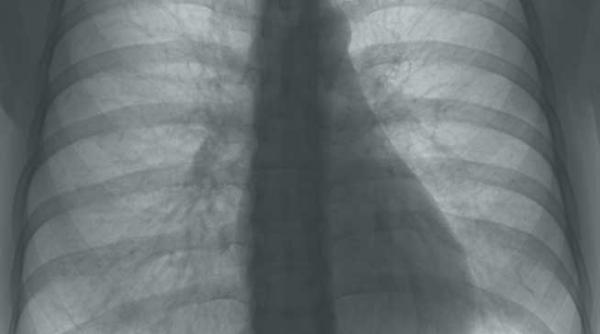

Cancerul, scos la iveală prea târziu. La 70% dintre pacienţii cu cancer pulmonar şi 60% cu cancer renal boala este descoperită în ultimele stadii

Halena arată bolile plămânului. Compuşii din aerul expirat pot indica dacă o persoană suferă de cancer pulmonar